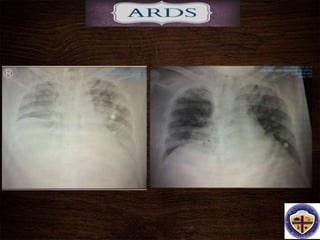

4th HOSPITAL DAY

6th HOSPITAL DAY

• #41 A representative anteroposterior chest x-ray in the exudative phase of ARDS shows diffuse interstitial and alveolar infiltrates that can be difficult to distinguish from left ventricular failure.